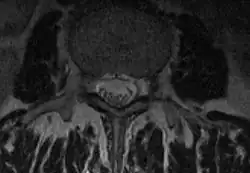

NMR-Darstellung der unteren Wirbelsäule. Der Duralsack ist als annähernd querovale, dunkle Struktur im Spinalkanal zu sehen. Die dunklen Tupfen darin sind die einzelnen, aus dem Rückenmark entstammenden Nervenwurzeln. In der dargestellten, weit unteren Etage der Wirbelsäule ist das Rückenmark selber nicht mehr zu sehen.

CT-Darstellung einer ISG-Arthrose. Der Duralsack und die beiden, seitlich und bauchwärts davon gelegenen Wurzeltaschen. Bei dieser Form der Darstellung kann man nicht zwischen Nervengewebe, Liquor und Dura unterscheiden.